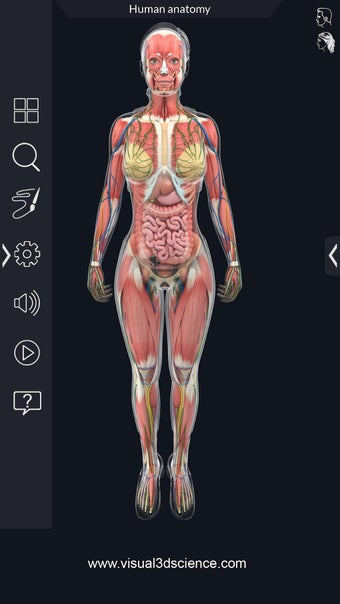

La anatomía humana es una aplicación educativa médica que te permite explorar el cuerpo humano desde todos los ángulos. Ofrece una mirada detallada a la anatomía de los diferentes sistemas, así como a los órganos y sus funciones. Es una referencia perfecta para estudiantes y profesores de medicina.

Puedes seleccionar cada parte del cuerpo por separado para ver su nombre o leer información relacionada. Puedes ocultar y mostrar cada parte del cuerpo, así como rotar 360° alrededor de un modelo 3D altamente realista. Puedes dibujar en la pantalla o compartir capturas de pantalla con tus amigos. Puedes encontrar la definición de cada parte del cuerpo y su anatomía.